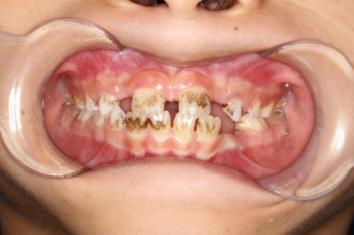

❸ 牙齿不齐:影响咬合关系,影响美观。

前

后